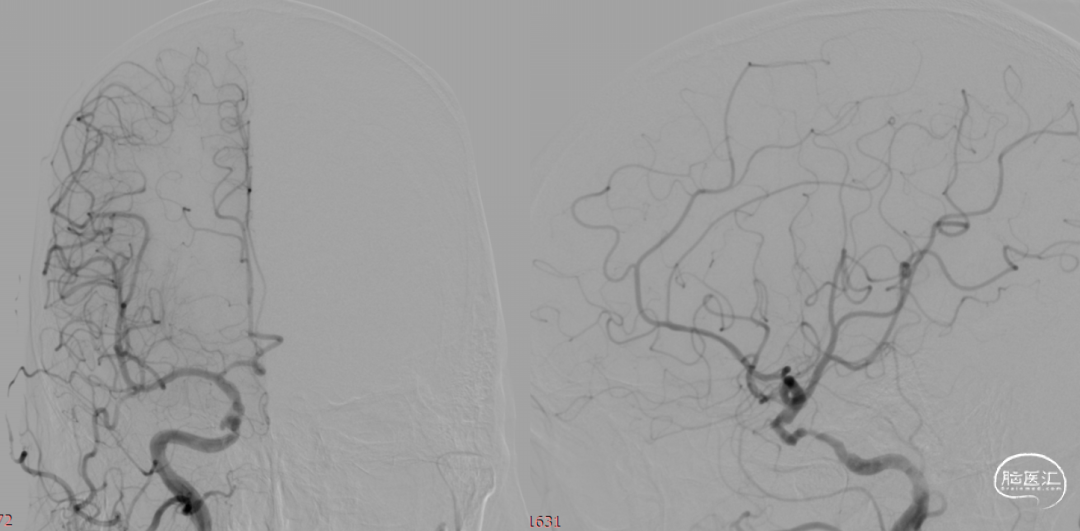

术前造影:

术后即刻。

术后即刻,可见动脉瘤瘤腔内血液滞留明显。

术后即刻,正侧位造影。